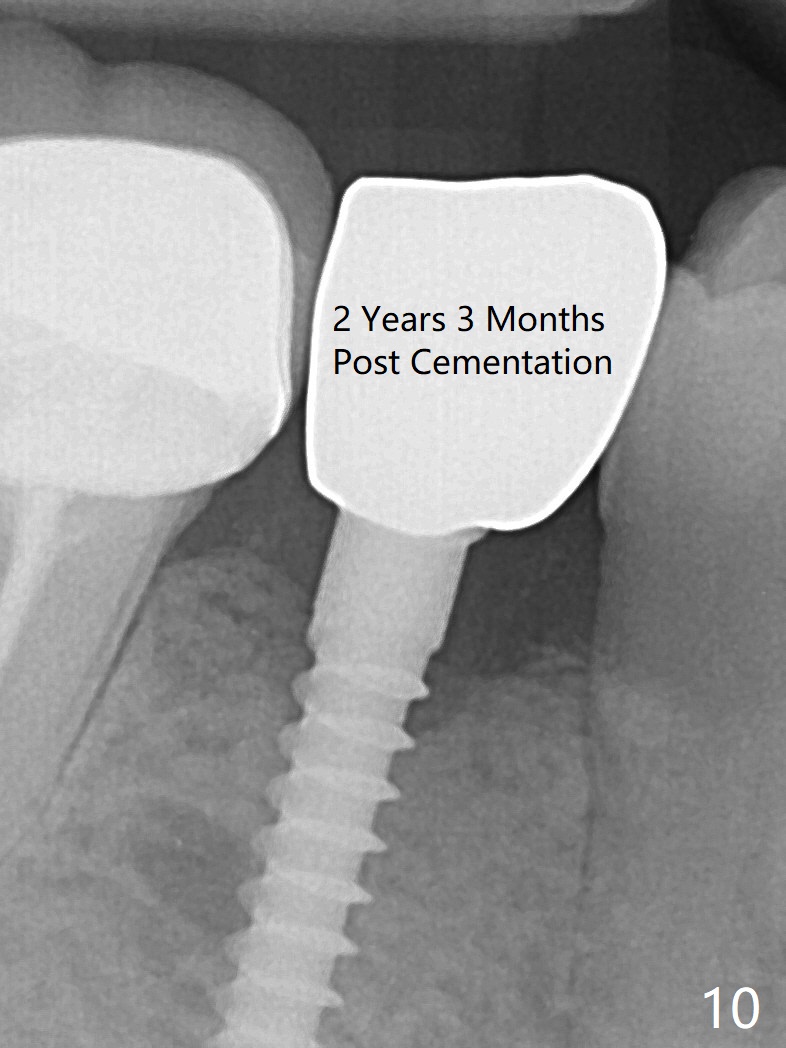

Preop photo shows the distal inclination of the tooth #28 (Fig.1).  The distal surface of the latter is reduced before incision for implant placement at #29 (Fig.2).  The buccolingual width is approximately 4 mm, as compared to 3 mm implant positioner (Fig.3).  After 1.2x10 mm osteotomy (Fig.5), the mesiodistal cortical bone is removed with a small high-speed fissural bur (Fig.4).  When a 2.5x12(2) mm 1-piece implant is placed (Fig.6), there is no buccal (Fig.7) or lingual plate perforation.  There is no postop paresthesia.  There is mild bone loss distal 4 months postop (Fig.8 *).  Take photos before and after permanent crown cementation to show increase in ridge width after bone graft and improvement in gingival health after provisional modification.  Take PA and/or BW post cementation to show that the distal bone resorption (Fig.8 *) is partially due to angulation.  No continuous bone loss 15 months post cementation (Fig.9).  There is mild bone resorption mesially 2 years 3 months post cementation (Fig.10).  The soft and hard tissues remain healthy 4 years 3 months post cementation (Fig.11,12).